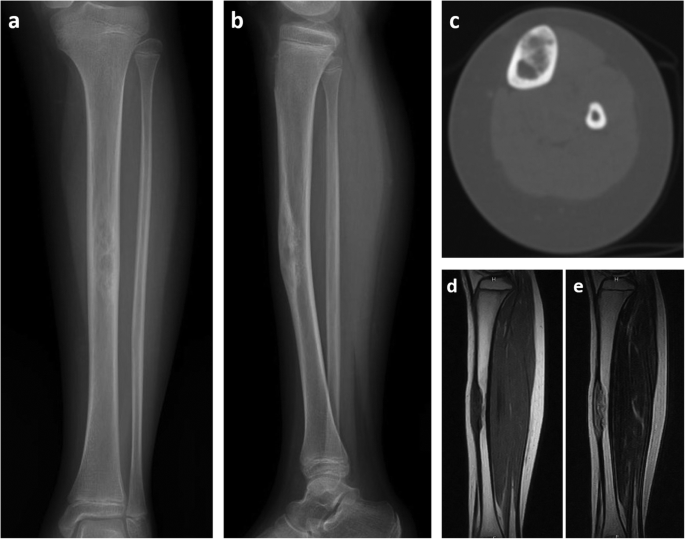

A 10-year-old girl presented with a 3-month history of pain in her left lower leg after bruising. She had no medical conditions and was physically active. On physical examination, she had a bony lump in the middle third of the left tibia with some tenderness. An X-ray of the left leg showed a 6-cm mass with multiple osteolytic and sclerotic lesions in the thickened anterior diaphysis of the left tibia (Fig. 1a, b). No periosteal reaction was observed. Computed tomography revealed that the 6-cm mass was confined to the cortex of the tibia (Fig. 1c). On magnetic resonance imaging (MRI), it was heterogeneously hypointense and isointense on a T1-weighted sagittal image and heterogeneously hyperintense on a T2 sagittal image; it measured 63 mm in the tibia with incomplete involvement of the marrow cavity (Fig. 1d, e). The mass was highly suspected to be an OFD, and open biopsy was performed.